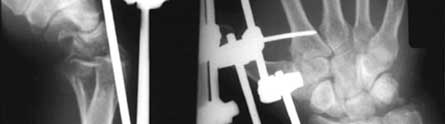

Serious fractures are often treated by inserting metal pins through the skin into the bone and stabilised by a metal frame.

Pins used to mend broken bones can often lead to infection. Up to 40 per cent of patients being treated in this way develop infections, which can in the worst cases, lead to osteomylitis (bone infection) and septicaemia.